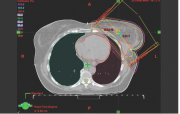

| 12:27, 3 במרץ 2015 | Irradiation4.png (קובץ) |  |

158 קילו־בייטים | Motyk | 1 | |

| 20:10, 2 במרץ 2015 | Irradiation3.png (קובץ) |  |

150 קילו־בייטים | Motyk | 1 | |

| 19:38, 2 במרץ 2015 | Irradiation2.png (קובץ) |  |

217 קילו־בייטים | Motyk | 1 | |

| 19:34, 2 במרץ 2015 | Irradiation1.png (קובץ) |  |

468 קילו־בייטים | Motyk | 1 | |

| 06:47, 1 במרץ 2015 | Radiotherapy2.png (קובץ) |  |

231 קילו־בייטים | Motyk | 1 | |

| 06:41, 1 במרץ 2015 | Radiotherapy1.png (קובץ) |  |

261 קילו־בייטים | Motyk | 1 | |